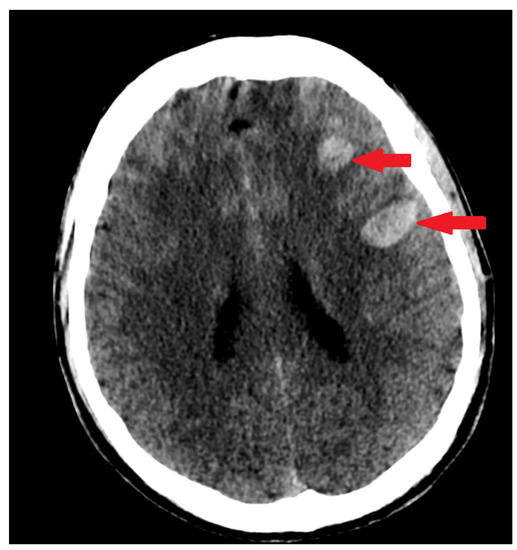

3.5. Imaging Studies